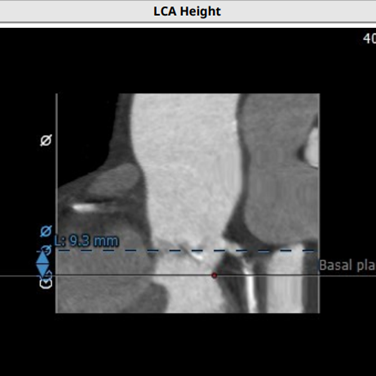

术前检查显示患者左冠开口较低,只有9.3mm